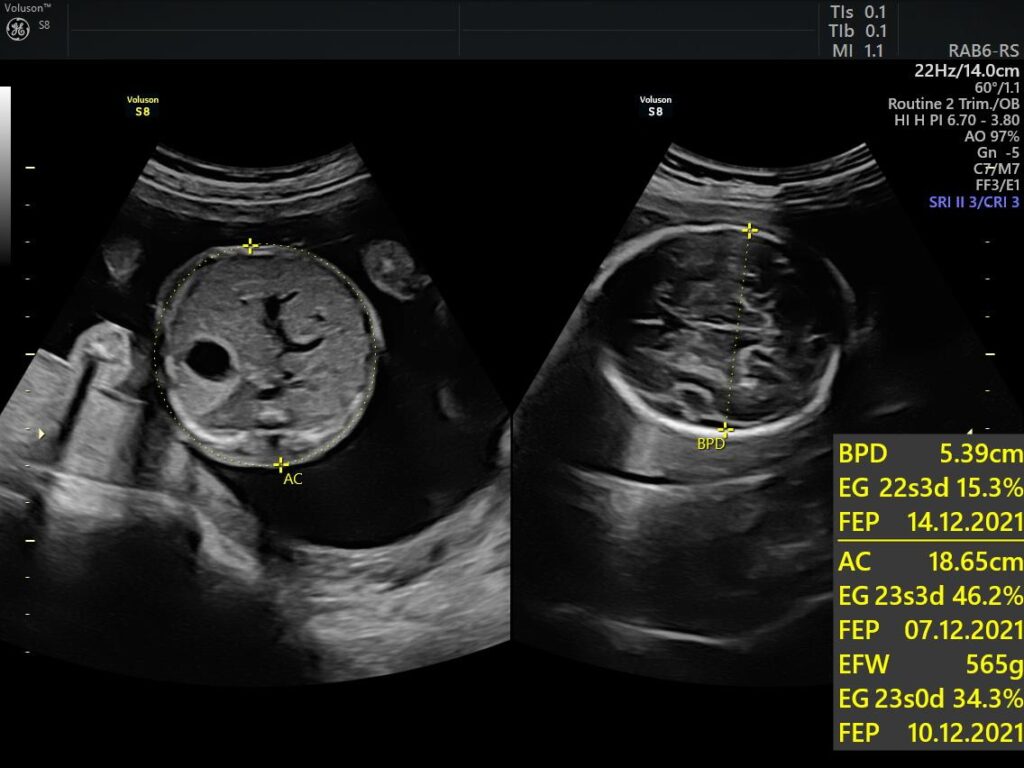

Ejemplos Ultrasonido: 4a Dimensión